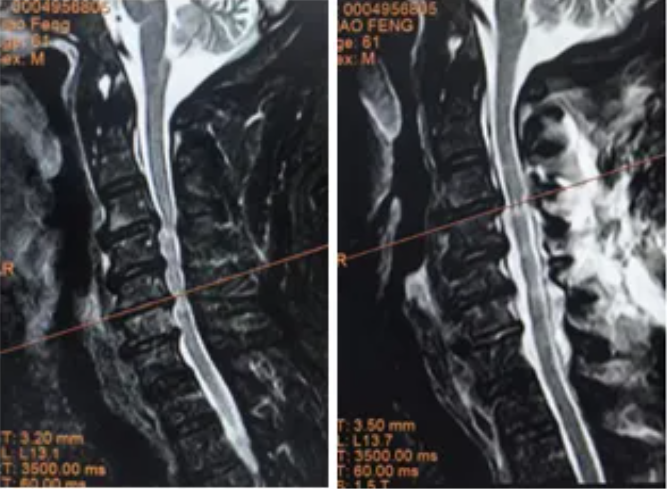

肖先生(化名)曾长期被四肢麻木、写字颤抖、行走不稳困扰,保守治疗效果不佳,症状持续加重。经过多方求医,来到郑州大学第五附属医院,经颈椎核磁检查显示:C3-C7节段严重椎管狭窄,椎间盘突出导致脊髓严重受压。

▲ 术前MRI

▲ 术前MRI ▲ 术后MRI

术后影像显示患者椎管空间明显扩大,脊髓压迫解除,四肢麻木症状消失,肌力逐渐恢复,生活质量显著提升。